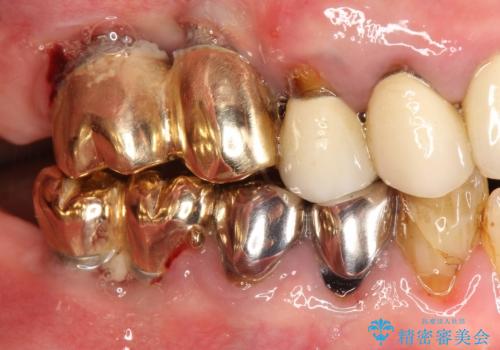

薄い骨にもインプラントを スプリットクレスト+ショートインプラントの応用

- 破折により保存不可能となった歯を抜歯後、待時してインプラントを計画した。

骨が薄く、インプラントの径に耐え得ないと判断したためスプリットクレストにより骨幅を拡大しインプラントを埋入した。